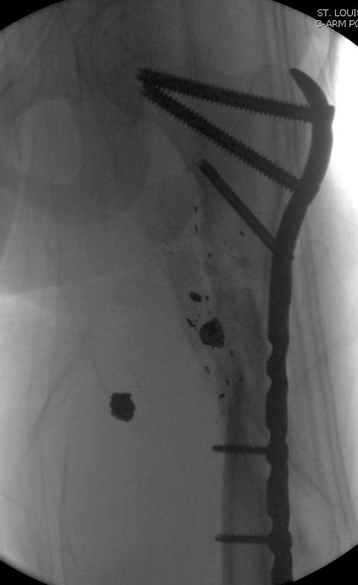

Перелом низкоскоростным оружием, типа пистолетного, так что не стали гоняться за пулевыми фрагментами. С нервом пока подождем, иногда нерв восстанавливается если не прямое попадание в нерв, а "сотрясение" (shock wave injury).

Из всех типов фиксации взяли малоинвазивную технику мостовидной пластиной, использовали Locking проксимальную Synthes пластину.